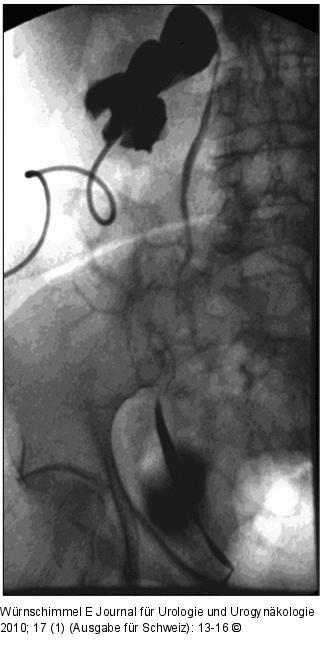

Abbildung 4: Single-Incision Laparoscopic Surgery Antegrade Pyelographie einer infizierten, gestauten Wanderniere über eine Nephrostomie (Aufnahme im Liegen) |

Abbildung 4: Single-Incision Laparoscopic Surgery

Antegrade Pyelographie einer infizierten, gestauten Wanderniere über eine Nephrostomie (Aufnahme im Liegen) |